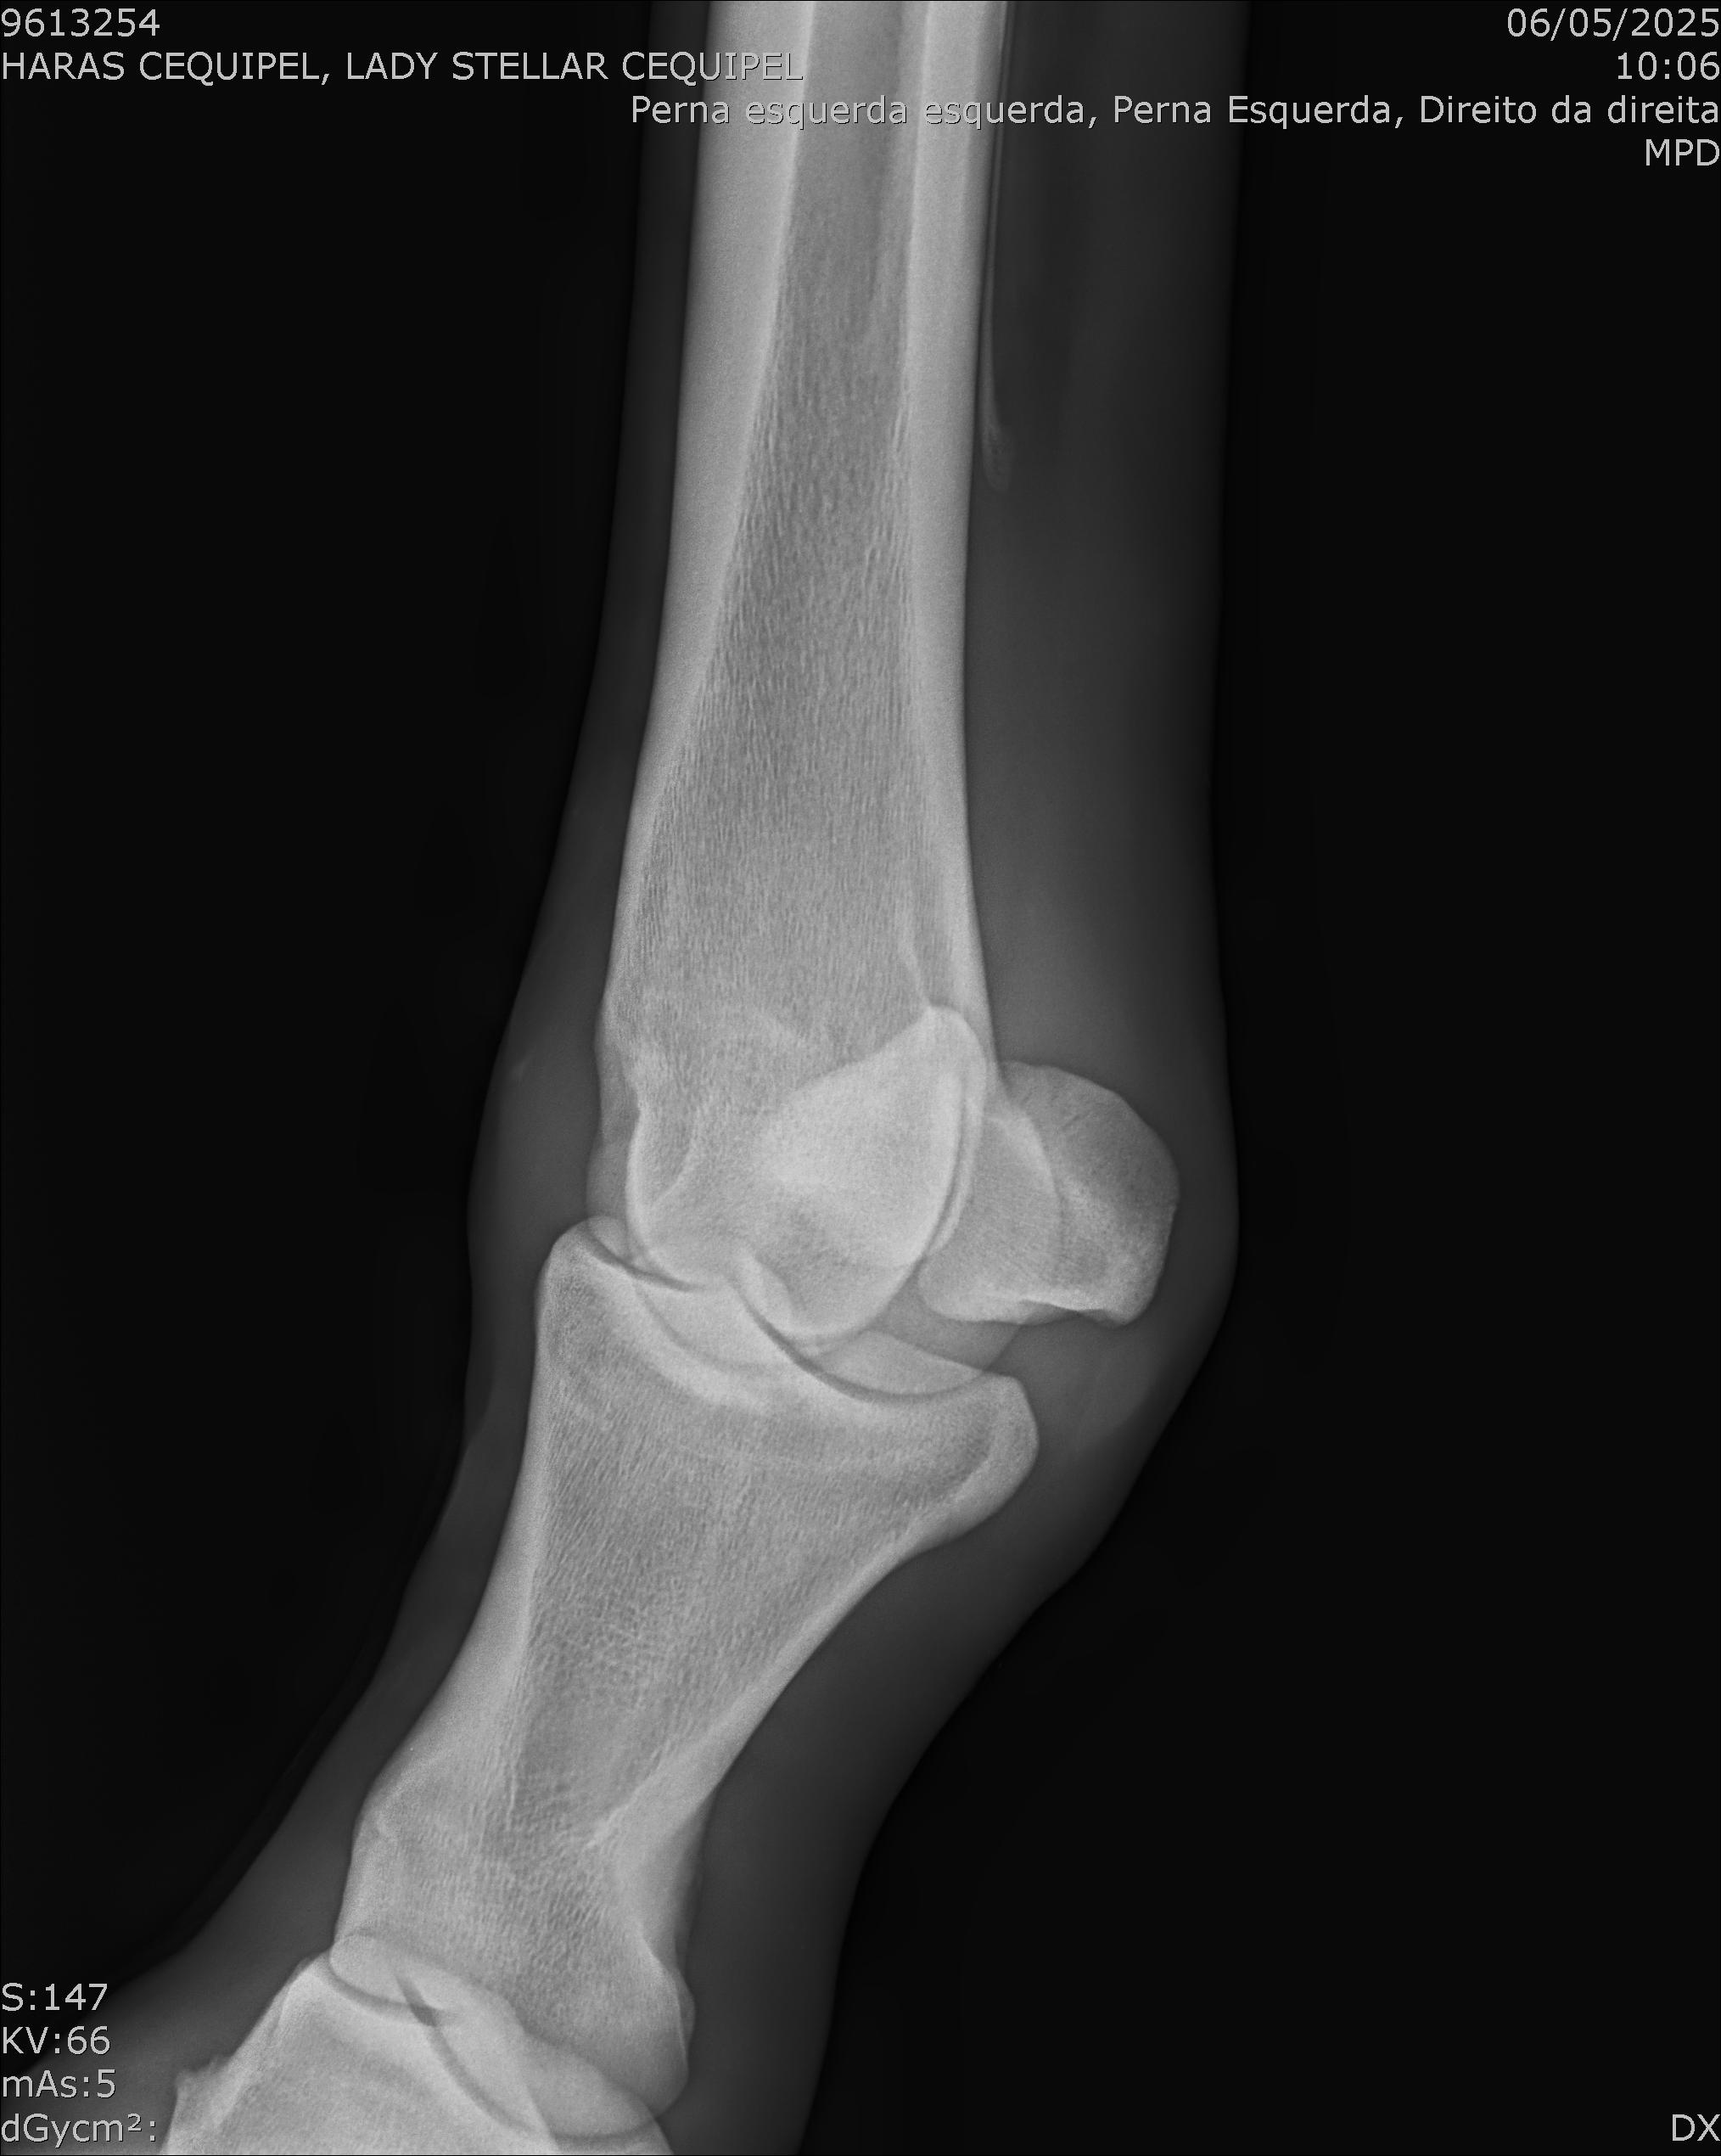

:: RAIOS-X DO LOTE